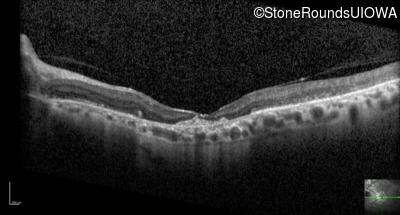

Optical Coherence Tomography - Right - 20/125 -2

Exemplar / OCT Stack

OCT Stack